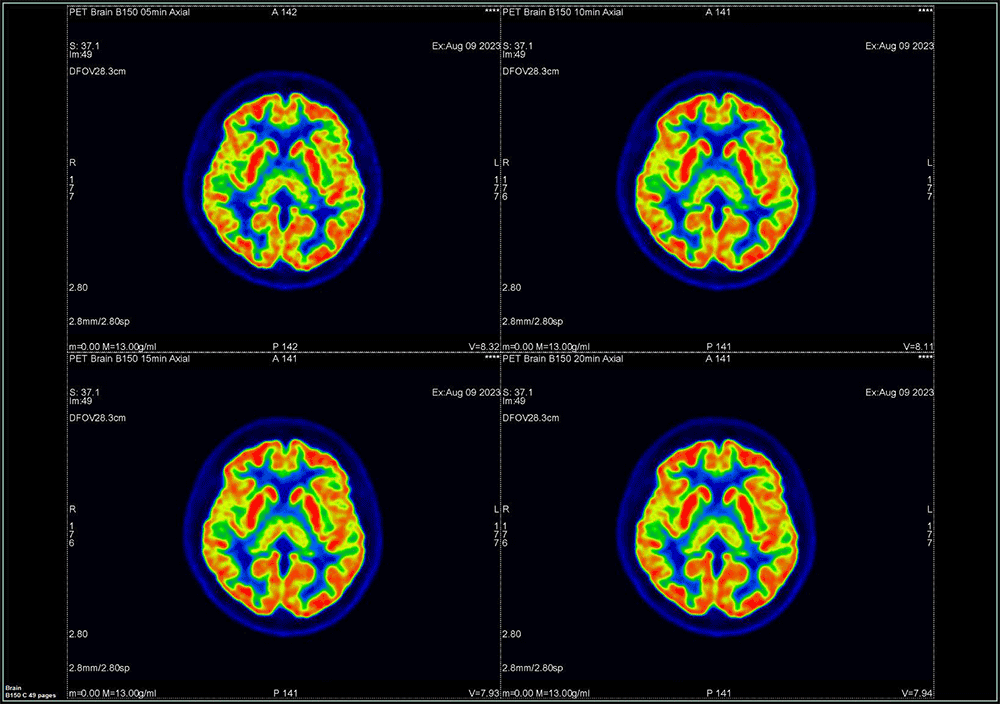

① OSEM法

OSEM画像をFig.5に示す。分解能の視覚評価においてマトリック数192以上では差を認めませんでした。

Fig5. 描出能の視覚評価 OSEM法